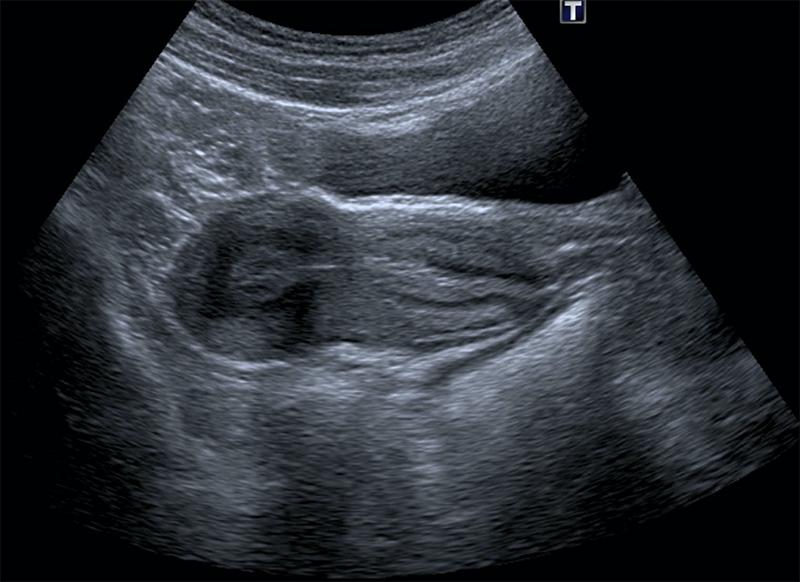

Echographie Pelvienne

Procédure d’imagerie médicale non invasive qui utilise des ondes sonores à haute fréquence pour produire des images en temps réel des organes pelviens chez les femmes.